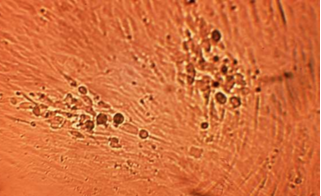

Diagnostic CPE of Respiratory Syncytial Virus (RSV)

RSV causes syncytia (fused multi-nuclear cells) primarily in the HL cells. HDF cells may also be affected but the CPE usually appears later and appears as minor patches of cell disintegration along monolayer borders.